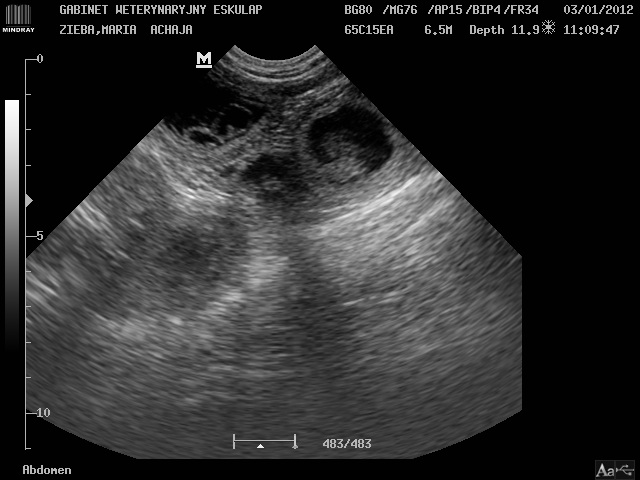

Pierwsze USG

A jednak są!!! W achajowym brzuszku głowica aparatu USG bez problemu odnajduje co najmniej 3 piłeczki!!